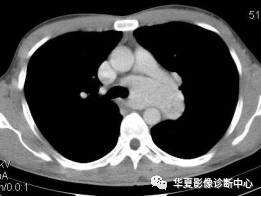

男性,32岁。无明显原因胸闷不适3月,胸片示纵隔及左肺门占位。

【CT征象】纵隔主肺动脉窗内见团状软组织肿块,最大截面约5.0cmX4.0cm,密度均匀,动脉期呈中度强化,延迟扫描呈明显强化,接近同期血管密度;左肺动脉干及左主支气管略受压。

【CT诊断】 ①巨淋巴结增生症;②淋巴瘤;③结节病;④淋巴结结核。

【最后诊断】纵隔巨淋巴结增生症。